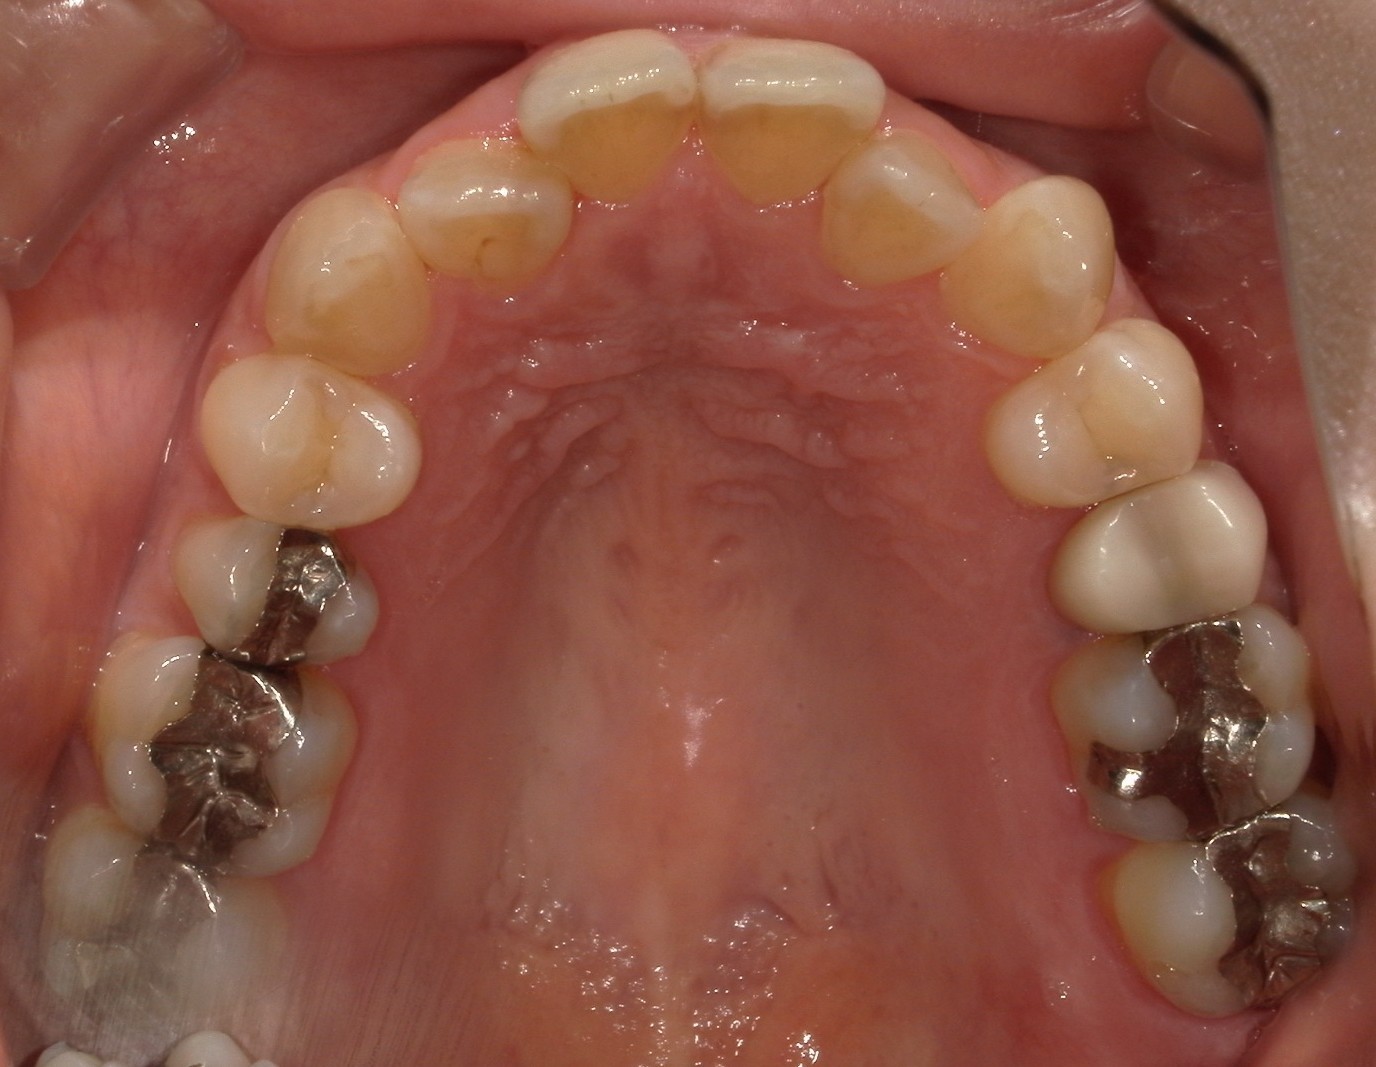

前歯だけの矯正の症例紹介③

Before

主訴

前歯の歯並びを改善したい。

治療内容

後ろに引っ込んでいる左上側切歯は抜歯し、ワイヤー矯正で治療しました。

治療費

115,500円(税込)(リテーナー込み)

治療期間

3か月

通院回数

5回

想定されたリスク

※左右対称にならない

左上側切歯を抜歯したほうが見た目は左右対称に見えやすかったが、左上犬歯を抜歯すると側切歯を動かす距離が多くなってしまい治療期間が長引くのと歯根にダメージを与える可能性があったため、患者様と相談し、側切歯のほうを抜歯しました。